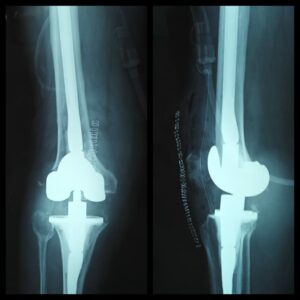

History: 75 yrs old male was unable to walk or perform basic leg movement due to an adverse knee inflammation from a failed primary knee replacement implant

Case: Dr. Amyn Rajani had conducted a revision of primary knee replacement surgery for this man as the implantations from the previous knee replacement surgery done elsewhere loosened and caused several damages to his knee joint. Referring surgery to a well-experienced and highly trained surgeon becomes a necessity in such cases. It is important that we avoid considering surgery from young, untrained surgeons and opt for those who have high experience and expertise in the given field of surgery.